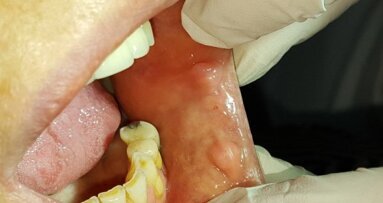

25-letnia pacjentka, ogólnie zdrowa, niepaląca zgłosiła się w celu uzupełnienia braku zębów 24-26. Zaplanowano podniesienie dna zatoki szczękowej metodą otwartą z jednoczesnym wprowadzeniem 2 implantów, a po okresie gojenia most 24-26 (Ryc. 18 i 19).

Po odpreparowaniu płata przygotowano łoże implantu w miejscu 24 i wprowadzono implant BEGO Semados S3, 25L 11,5. Następnie z użyciem SLA Kit wykonano okienko w ścianie zatoki. Podczas preparacji błony śluzowej zatoki doszło do niewielkiej perforacji, którą zaopatrzono błoną kolagenową BEGO Membrane. Do zatoki wprowadzono BEGO Oss, przygotowano łoże implantu 26 i wprowadzono implant BEGO Semados S3, 75L 11,5. Jako śrubę zmykającą zastosowano śrubę typu Engelke, która uniemożliwia przemieszczenie implantu w kierunku światła zatoki szczękowej. Wykonano boczną augmentację w okolicy 24 materiałem BEGO Oss oraz całość pokryto błoną kolagenową BEGO Membrane. Założono szwy nieresorbowalne (Ryc. 20-27).